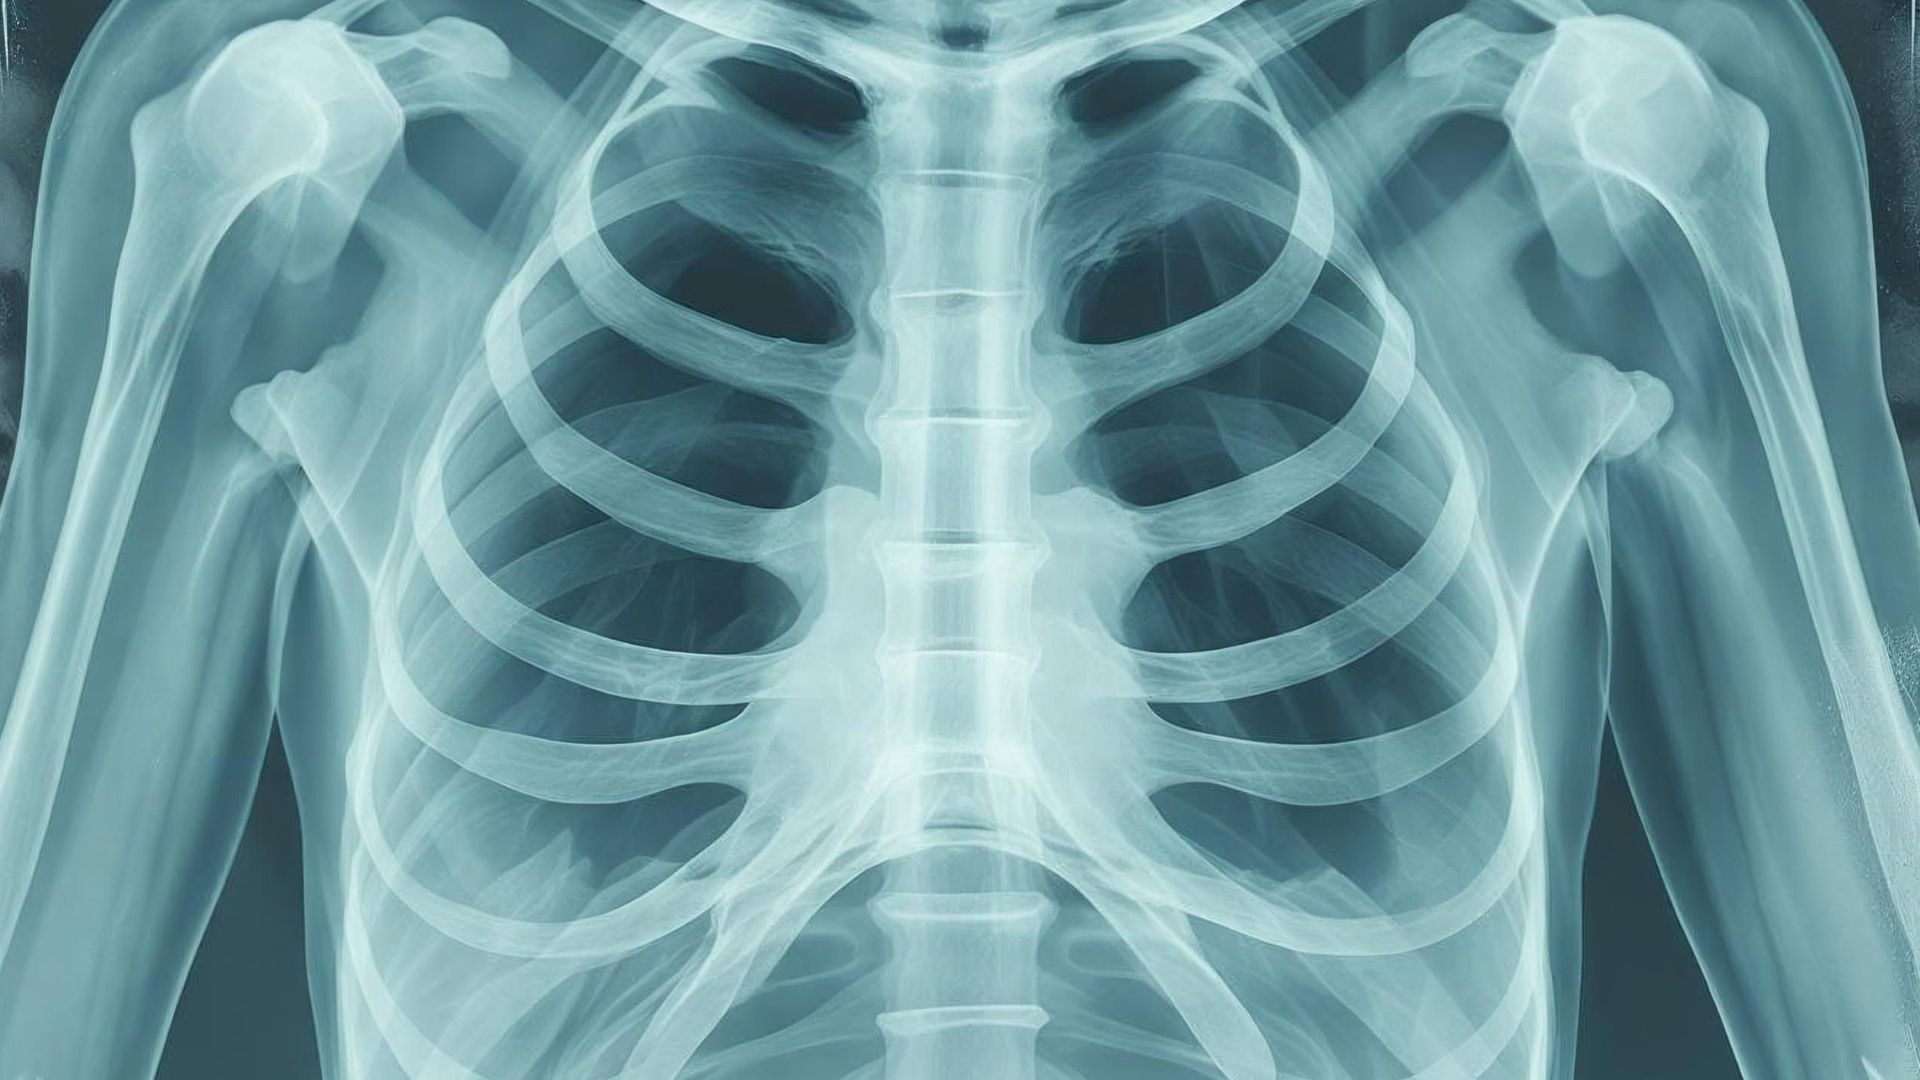

Hiểu rõ cấu trúc giải phẫu xương sườn không chỉ hỗ trợ sinh viên y khoa, kỹ thuật viên chẩn đoán hình ảnh và chuyên gia y tế phân tích chính xác các hình ảnh như X-quang, mà còn giúp mỗi người tự nhận biết cấu trúc lồng ngực của mình. Từ đó, bạn có thể chủ động phòng tránh các tổn thương và phát hiện sớm những bất thường liên quan đến vùng ngực. Hãy cùng bài viết dưới đây tìm hiểu thông tin chi tiết về xương sườn nhé.

U xương sườn có thể lành tính hoặc ác tính, triệu chứng thường mơ hồ, đôi khi chỉ là đau âm ỉ kéo dài hoặc phát hiện khối cứng bất thường ở lồng ngực. Việc chẩn đoán cần kết hợp hình ảnh học như X-quang, CT, MRI và sinh thiết để xác định chính xác. Tùy loại u, bác sĩ sẽ lựa chọn điều trị bằng phẫu thuật, xạ trị hoặc hóa trị. Việc phát hiện sớm giúp cải thiện tiên lượng rõ rệt.

U xương sườn thường được chẩn đoán dựa trên kết quả X-quang và sinh thiết